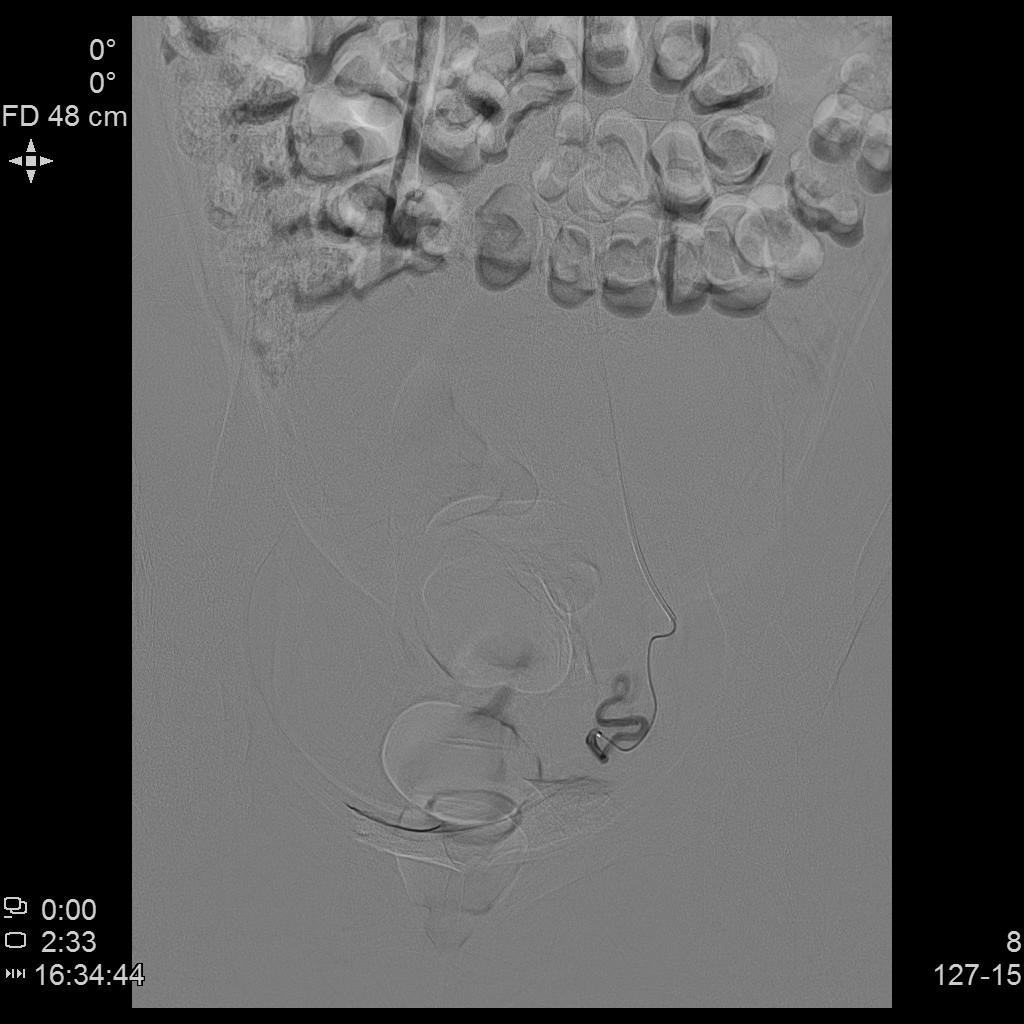

- 栓塞术后复查造影显示左侧子宫动脉分支末梢未见显示

- 术后桡动脉止血器压迫止血6~8小时,患者术后无需长时间卧床、下肢制动,舒适度大大提升,利于术后快速康复。

桡动脉压迫止血器